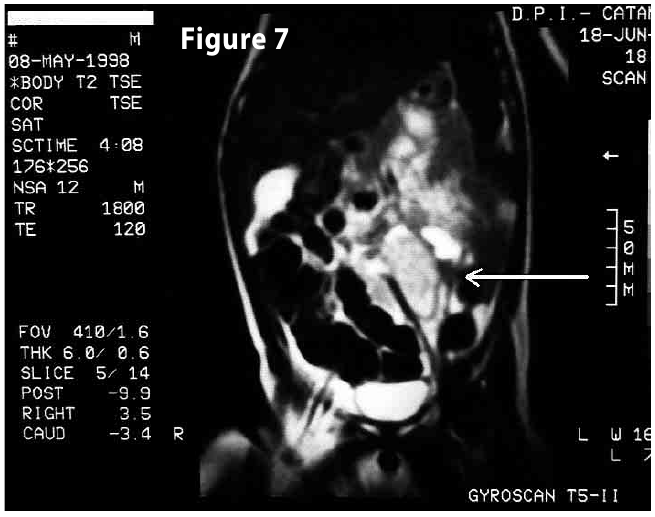

Figure7